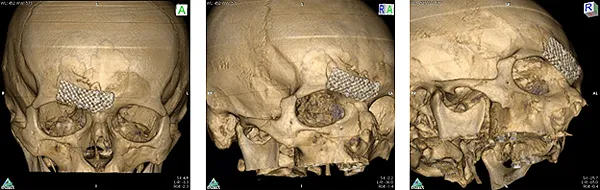

Открытая репозиция передней стенки лобного синуса, остеосинтез передней стенки лобного синуса титановым экраном

Спиральная компьютерная томография после операции: